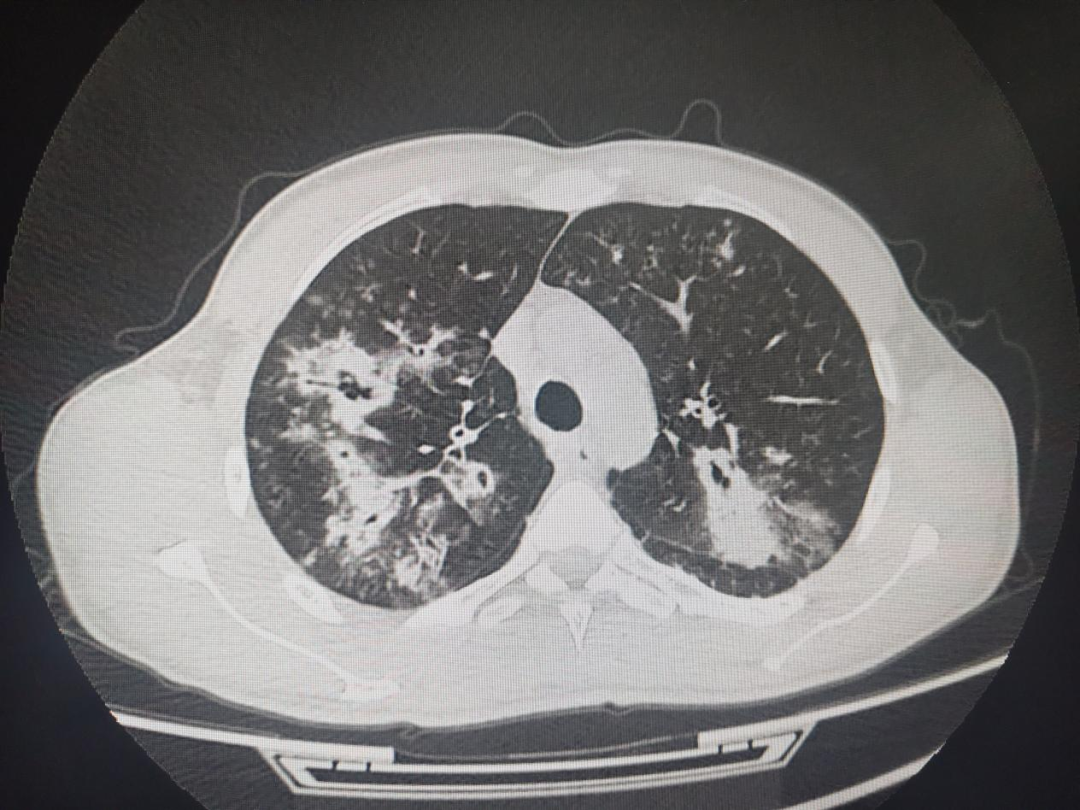

近日,泰安市中心医院急诊内科成功引入并开展了一项前沿医疗技术:纤维支气管镜下肺泡灌洗术,为急性肺部感染患者带来了更为精准、高效的治疗方案,标志着医院在急性感染救治领域迈出了重要一步。

急性肺部感染,如吸入性肺炎、重症社区获得性肺炎等,作为急诊科的常见病与多发病,其治疗效果直接依赖于病原体的快速、准确诊断。然而,传统痰培养方法易受口腔菌群污染,导致病原体检出率低,可能引发误诊或治疗延误。相比之下,纤维支气管镜灌洗术通过直接获取下呼吸道分泌物——支气管肺泡灌洗液(BALF),不仅有效弥补了传统痰培养的局限性,更通过直接清除气道内的病原体及分泌物,显著提升了患者的康复速度与治疗效果。

据研究显示,采用肺泡灌洗液进行检测的患者,病原体阳性率高达80%以上,远超常规痰培养组的30%-50%,为急诊医生提供了更为可靠的诊断依据。在退热时间、咳嗽咳痰缓解时间、住院天数等关键指标上,纤维支气管镜灌洗术均展现出显著优势,优于常规治疗。